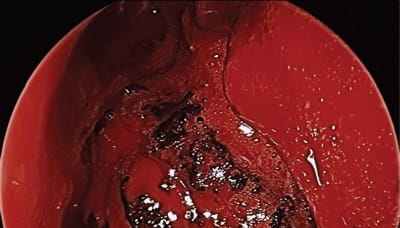

Endoscopic view of the left nasal cavity. Endoscopic view of the left nasal cavity. The inferior turbinate has been resected, the maxillary sinus has been opened widely, and the ethmoid cavity has been dissected. The mass is centered within the pterygopalatine fossa with expansion in all orientations.